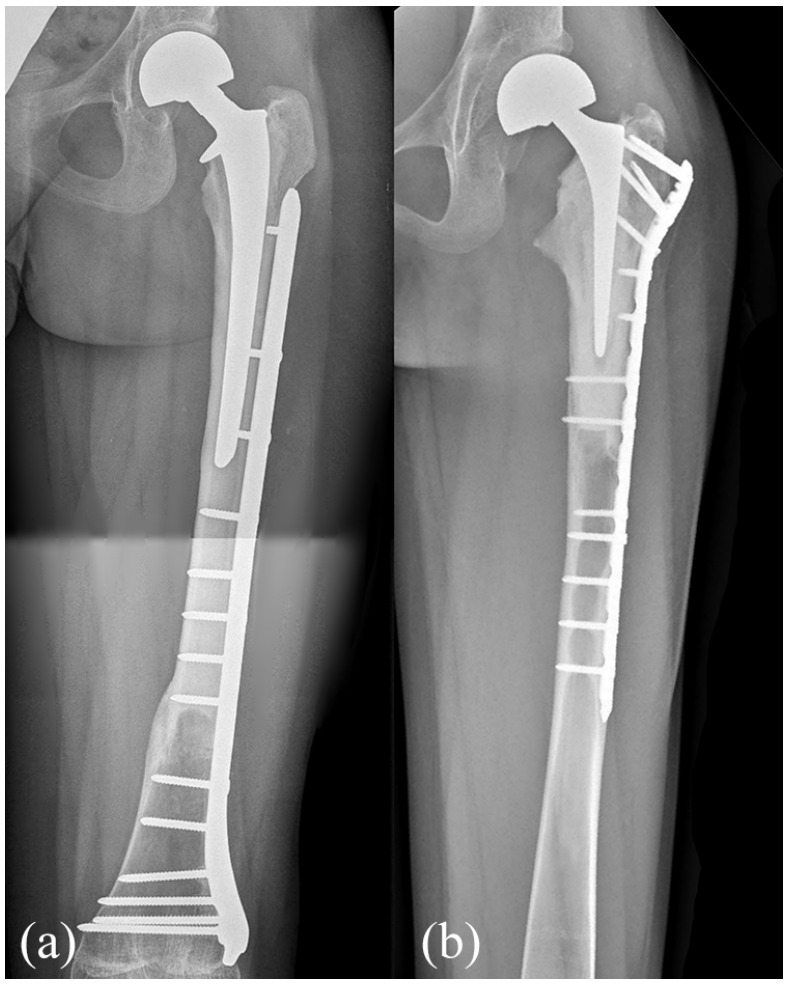

Methods: We reviewed 10 pediatric patients treated with proximal femur resection for a primary bone tumor and reconstruction with short stem allograft-prosthesis composite, with at least 24 months follow-up. The median age was 9 years (4-13) at surgery. The mean resection length was 15 cm (6-29). In six cases, fixation was performed with a short plate positioned under the great trochanter while in four cases a long plate extended over the great trochanter was employed.

Conclusions: Allograft-prosthesis composites with short stem and compression plate represents an effective reconstructive option after proximal femur resection for primary bone tumors in growing patients, preserving bone stock. The use of a compression plate extended over the greater trochanter seemed to reduce failure rate.